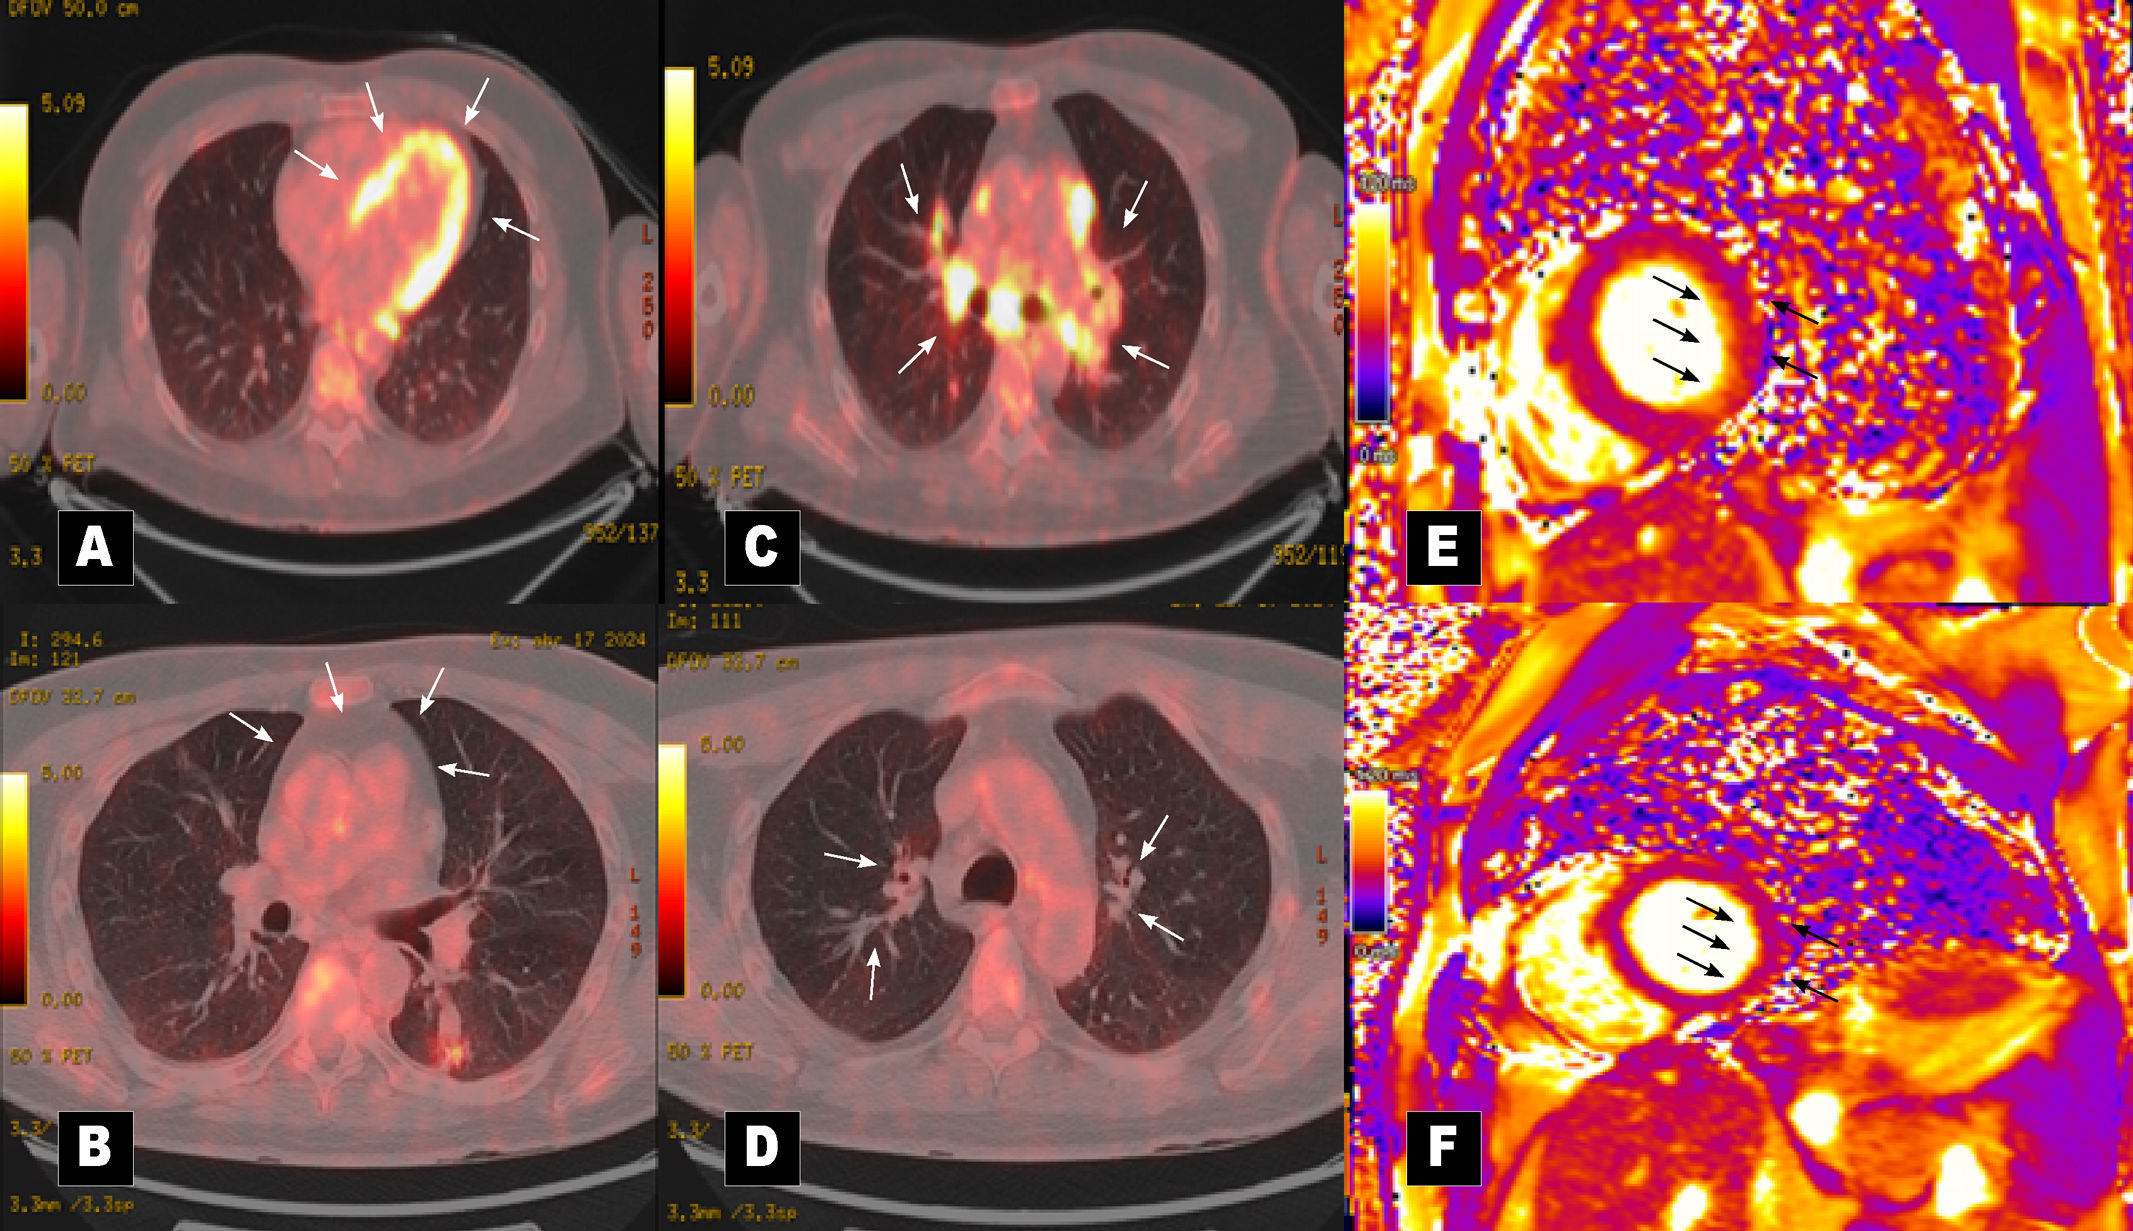

Ventricular extrasystoles secondary to mitral valve prolapse as an initial manifestation of cardiac sarcoidosis

Extrasístoles ventriculares secundarias a prolapso de la válvula mitral como manifestación inicial de sarcoidosis cardíaca